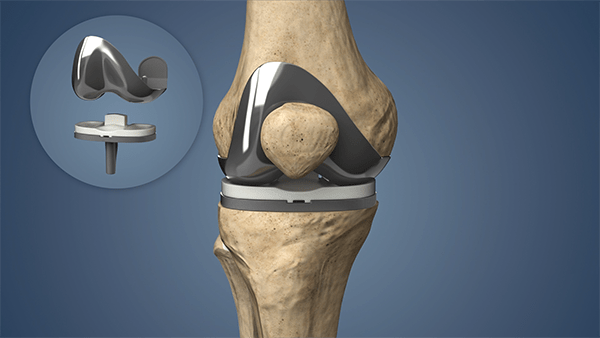

Which Are the Best Knee Replacement Options in South Bangalore?

Choosing a hospital for knee replacement surgery can feel overwhelming. With so many clinics and options, how do you know which one offers genuine care

HOW LONG DOES A KNEE REPLACEMENT REALLY LAST?

Are you planning to get knee replacement surgery and wondering about the outcome and how long it will last? Knee replacement is a major procedure,

Restore Mobility and Improving Quality with Joint Replacement Surgery

How important is joint replacement surgery when your daily life is disrupted by pain and limited movement? If you’re someone who’s been struggling to walk,